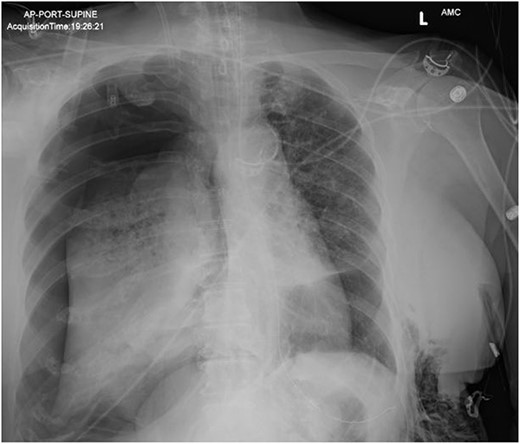

In the operating room (OR), the patient underwent intubation for TBNA using the Monarch® robotic bronchoscopy platform. Nine needle aspirations were obtained from the third-order RLL bronchi with each aliquot subjected to rapid on-site examination. While awaiting results, the patient developed retching, hemoptysis, bronchial bleeding from the superior segment of the RLL lobe and hypotension. The bleeding was managed with ice-cold saline and epinephrine. The patient required aggressive resuscitation with crystalloid, blood products and vasopressor therapy. She was transferred to the ICU where she remained intubated for ongoing resuscitation. In the ICU, the patient developed recurrent hypotension. Chest X-ray (CXR) revealed a right-sided pneumothorax (Fig. 1) that was treated with a small-bore pigtail chest tube and resulted in immediate improvement of her tension physiology. The pneumothorax resolved on repeat chest film while the patient remained intubated and sedated (Fig. 2).

AP upright chest radiograph showing placement of right-sided chest tube and resolution of right pneumothorax.